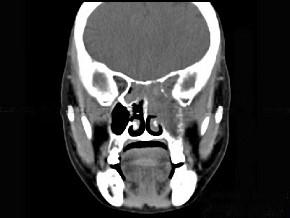

问题 男性50岁,涕中带血半年,体检发现右侧颈部多个硬结,CT扫描如图所示,请选择正确的描述和结论 ( )

选项 A、考虑为右侧筛窦黏液性囊肿 B、考虑为右侧筛窦癌 C、软组织影累及对侧筛窦、右侧上颌窦 D、右侧眶内壁、上颌窦壁及颅底骨质破坏 E、右侧筛窦内见软组织块影,边缘不规则

答案 BCDE